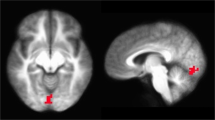

Perceptual grouping by spatial proximity takes advantage of the natural phenomena by which dots in rows can be perceived as “lines” dependent upon their relative horizontal and vertical arrangement (see Fig. 1a). As the horizontal to vertical ratio approaches one, the ability to perceive these lines disappears. Work by Kurylo et al. (2007) has shown that medicated schizophrenic patients require more “signal” than typical patients to observe these lines, a finding in line with similar perceptual tasks like contour integration or coherent motion (Green et al. 2009). While contour integration, coherent motion, and perceptual grouping by proximity are all subtly different, they share in common an integration element that is thought to be dependent upon areas early in the visual cortex (V1-V2). Moreover, Kurylo and Gazes (2008) has reported that rodents can learn to discriminate based upon stimuli of this type and that the discrimination is dependent upon an intact visual cortex as well.

Here, we adapt the perceptual grouping paradigm used by Kurylo et al. to a touchscreen environment (Kurylo et al. 2007; Kurylo and Gazes 2008; Ward et al. 2013). To do this, we initially trained rats to discriminate horizontal versus vertical dot lines. Once animals were performing this discrimination, they were presented with stimuli of varying difficulty (12 levels; Fig. 1b) where difficulty increased as the horizontal-to-vertical ratio became closer to zero. Having established that animals could learn the task and that performance was dependent upon the horizontal to vertical ratio (Fig. 2), we then performed several pharmacological challenges. With these pharmacological challenges, we wanted to test two hypotheses: (1) NMDA-R antagonism will cause a shift in threshold for grouping by proximity (requiring more signal for grouping to occur), and (2) in accordance with the theory of excitation/inhibition balance, that decreasing neuronal excitation via stimulation of the GABAergic system will result in an improvement in perceptual grouping.

The perceptual grouping task is a simple visual discrimination in which subjects are required to select one of two stimuli. The stimuli are simple dot lattices in which dots are either presented closer together in the horizontal plane or the vertical plane. The stimuli can be expressed as a ratio of horizontal distance between dots against vertical distance, or spaced apart. As the space between horizontal dots and between vertical dots becomes smaller, the difference between horizontal and vertical presentations becomes greater and the stimuli become easier to discriminate. Conversely, as the distance between horizontal and vertical spacing between dots becomes more comparable, the stimuli are harder to discriminate (Figs. 1 and 2). This ratio is expressed as Log10 (Ratio), in order to enable results to be expressed graphically in regular steps. Twelve different horizontal and vertical stimuli, ranging from Log10 (Ratio) = 0.01 (hardest) to Log10 (Ratio) = 0.44 (easiest), were used in this study (Fig. 1b).